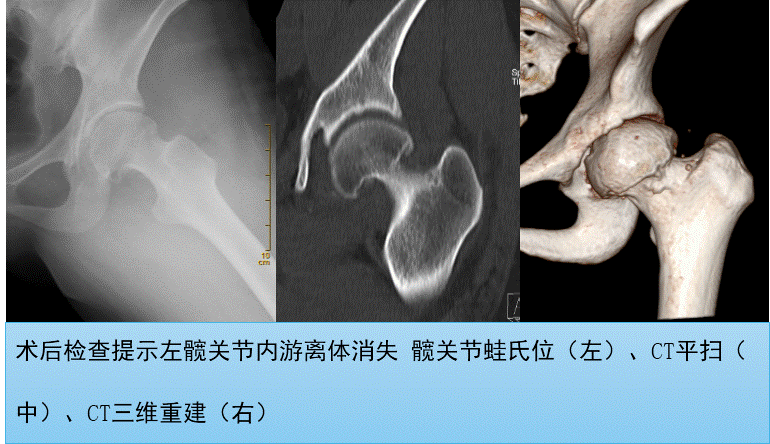

在曹女士手术的髋关节镜手术中探查发现关节腔内遍布多个白色游离体,应用特制的抓物钳一颗颗的夹出来,经个两个多小时辛勤“采摘”竟然取出了20颗大小不等的骨软骨性游离体,有的大如蚕豆,有的小如米粒。术中出血量不到10毫升,术后第二天就可以下地行走了,复查X线和CT后提示关节内游离体基本完全取尽。曹女士术后恢复十分良好,术后第三天便办理了出院手续,术后2周来院复诊拆线时已经完全恢复正常行走。